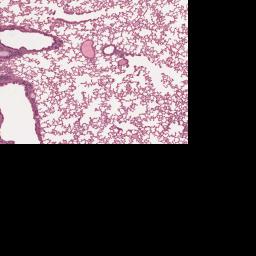

Index of /PathCampVirtualSlides/lung_post-mortem_clot/3